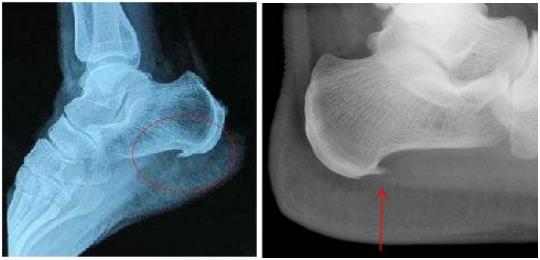

为什么脚后跟会长骨刺?

"骨刺"也叫骨质增生、骨赘。它是人体为弥补衰老磨损、不堪重负的关节而主动、代偿性增生的骨质。它能起到辅助固定、支撑的作用。常出现在骨质流失较为严重的老年人、更年期后妇女身上。

当然,不好好长的骨刺的确会导致脚后跟疼痛。

(2)跟骨骨折

对于正常人来说,跟骨是不容易骨折的。但若从高处坠落,或骨质流失严重人群的跟骨的确易骨折。若脚后跟疼痛的同时,还出现肿胀、皮肤淤紫甚至不能行走的情况,这种可能性很大。

此时要立即到骨科就诊。医生会通过X片等检查明确是不是骨折,如果确实有骨折,就需要石膏固定或者手术治疗。